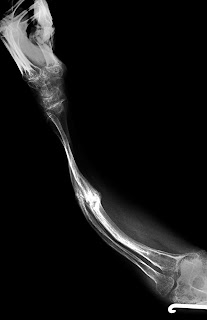

Throughout my life I have endured one hundred and ninety one broken bones, twenty-two surgeries and died twice due to complications during surgery. I have experienced both physical and mental pain due to my condition, Osteogenesis Imperfecta and because of the ways people have treated me. I am using my work to both help people become aware of these internal issues and to try and allow others to see life from my point of view.

Using both photographs and X-rays, I have created a full body self-portrait. My illustration conveys the narrative of my life through images of the broken bones that are the source my disfigurement. The X-rays speak of the pain in my past while the image of my skin speaks of me in the present. The titanium rods in my bones showing inner strength and ability to endure the pain. My eye looks out at the viewer and to the pain that is yet to come.

The tattoo on my right arm symbolizes my shattered bones with forty-eight ravens. Each raven represents 4 broken bones, my twenty-two surgeries are symbolized with plus signs, and my two deaths signified with feathers. Allowing the viewer to see my entire body down to the bone will remind them that we are all the same, just skin and bones.